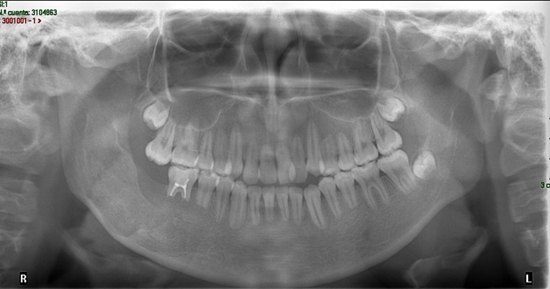

Paciente femenino de 9 años de edad de Valladolid, Yucatán, sin antecedentes patológicos sistémicos; que acude a la Clínica de Endodoncia de la UADY refiriendo traumatismo dental de 4 meses de antigüedad. Clínicamente presentó movilidad y estoma adyacente al diente 2.1, los incisivos anterosuperiores respondieron negativamente a las pruebas térmicas. Radiográficamente se observó formación radicular incompleta y lesiones periapicales en los incisivos centrales superiores.

Plan de tratamiento: revascularización en los órganos dentarios 2.1 y 1.1 y su posterior restauración. Se realizó el protocolo según Trope con dos modificaciones; se reemplazó el hipoclorito de sodio por la solución de agua superoxidada con pH neutro y se disminuyó el tiempo de irrigación de 20 a 5 minutos. A la semana del tratamiento inicial se observó que el estoma remitió, la movilidad cesó y la paciente se encontraba asintomática, se continuó el tratamiento. En los controles realizados durante 22 meses, la paciente se encontró asintomática, se observó el cierre apical del 1.1 y aumento de la porción radicular y disminución de la lesión apical en el 2.1.